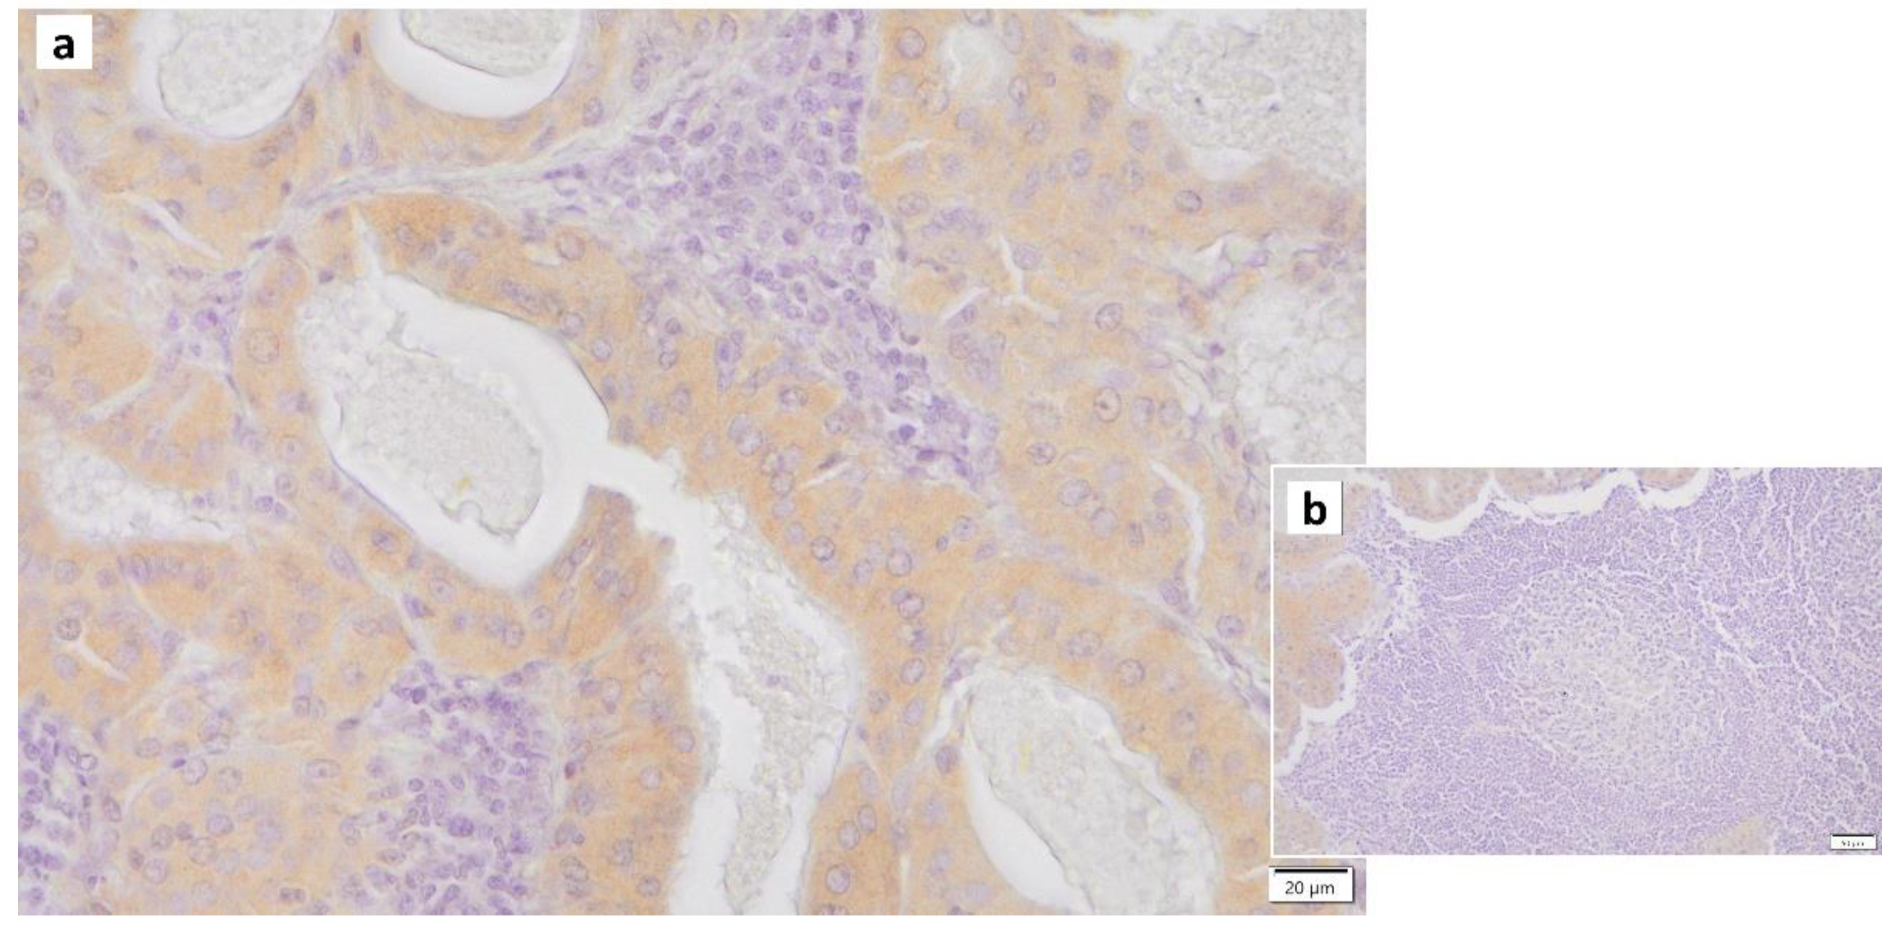

7. Mitochondrial Dysfunction and Warthin’s Tumor

- Mandic, R.; Agaimy, A.; Pinto-Quintero, D.; Roth, K.; Teymoortash, A.; Schwarzbach, H.; Stoehr, C.G.; Rodepeter, F.R.; Stuck, B.A.; Bette, M. Aberrant Expression of Glyceraldehyde-3-Phosphate Dehydrogenase (GAPDH) in Warthin Tumors. Cancers 2020, 12, 1112. [Google Scholar] [CrossRef]